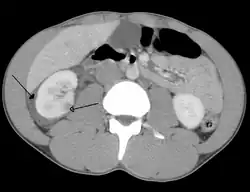

Abdominal trauma resulting in a right kidney contusion (open arrow) and blood surrounding the kidney (closed arrow) as seen on CT

Kidneys

A large hematoma (closed arrow) of the left kidney (open arrow)

The kidneys may also be injured; they are somewhat but not completely protected by the ribs.[6] Kidney lacerations and contusions may also occur.[13] Kidney injury, a common finding in children with blunt abdominal trauma, may be associated with bloody urine.[13] Kidney lacerations may be associated with urinoma or leakage of urine into the abdomen.[4] A shattered kidney is one with multiple lacerations and an associated fragmentation of the kidney tissue.[4]